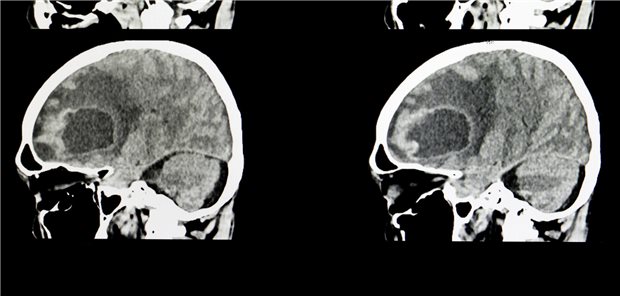

Glioblastom